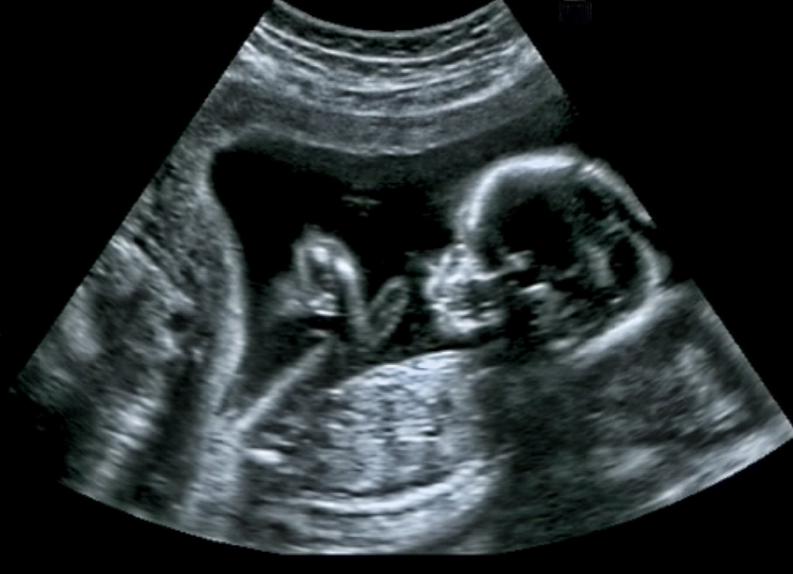

Ultrasound Scan

An ultrasound scan, sometimes called a sonogram, is a procedure that uses high-frequency sound waves to create an image of part of the inside of the body. An ultrasound scan can be used to monitor an unborn baby, diagnose a condition, or guide a surgeon…